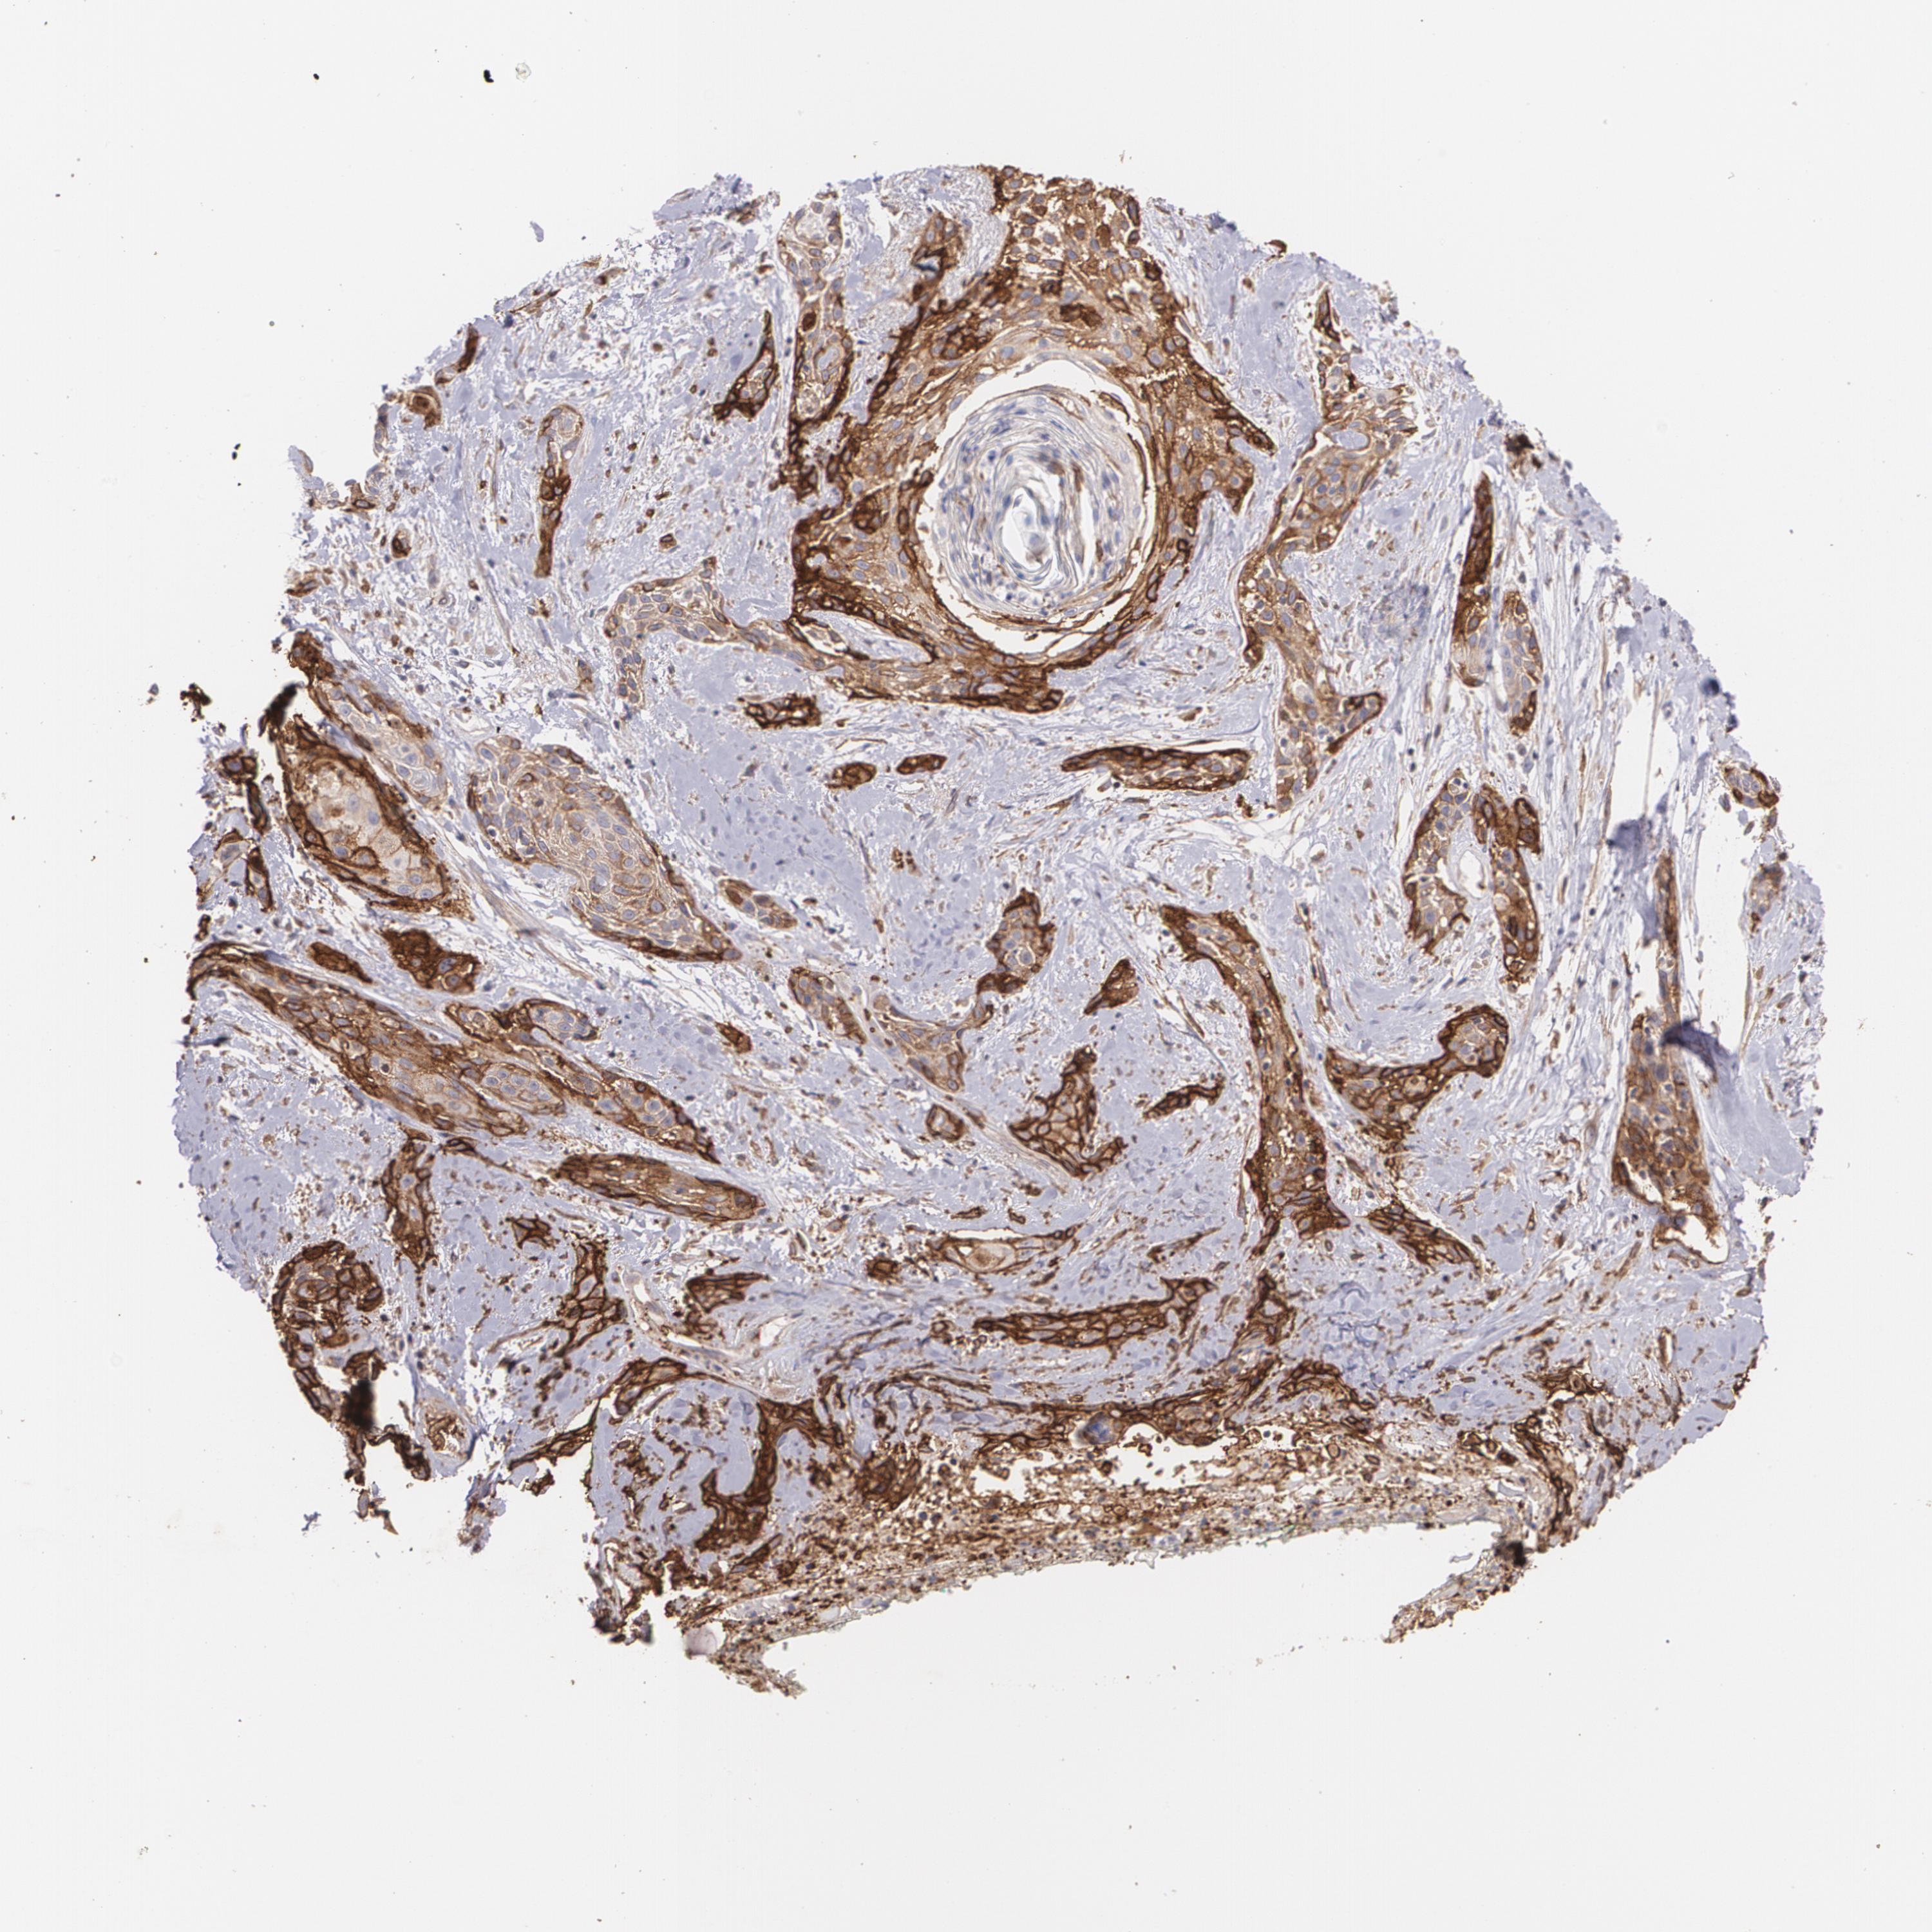

Basal cell and squamous cell cancer

SKIN CANCER - Protein expressioni

A mouse-over function shows sample information and annotation data. Click on an image to view it in a full screen mode. Samples can be filtered based on level of antibody staining by selecting one or several of the following categories: high, medium, low and not detected. The assay and annotation is described here.

Each image is clickable and will lead to virtual microscopy that enables deeper exploration of all samples and also displays staining intensity scores, fraction scores and subcellular localization as well as patient and tissue information for each sample.

Antibody HPA031345

Basal cell carcinoma